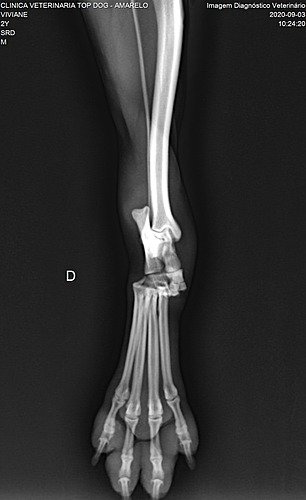

Meu nome é Peladinho, e me meti em confusão na rua brigando com outros 5 cães, na verdade não sei o que aconteceu, mas eles estavam me puxando de um lado para outro. Para minha sorte, quem me ajudou na Rua foram duas moças que estavam passando por ali nesse momento muito difícil para mim, pois ninguém mais conseguiu me ajudar. Eu senti muita dor, e estou muito machucado, então elas me levaram ao medico para que eu pudesse ser examinado, com a briga acabei tendo uma luxação articular, (fratura de Lisfranc) no meu pezinho, e agora só poderei andar fazendo uma cirurgia que precisa de pinos, e que é muito cara. Por isso preciso da ajuda de vocês pra fazer essa cirurgia o mais rápido possível, pois posso piorar. Como não tenho lar, essas moças estão me ajudando com essa vaquinha para poder arrecadar esse dinheirinho.

Deixo as imagens dos exames e o valor do procedimento, no valor de 3.500 já estou contando a medicação pós cirúrgica e as taxas cobradas para poder postar essa vaquinha.